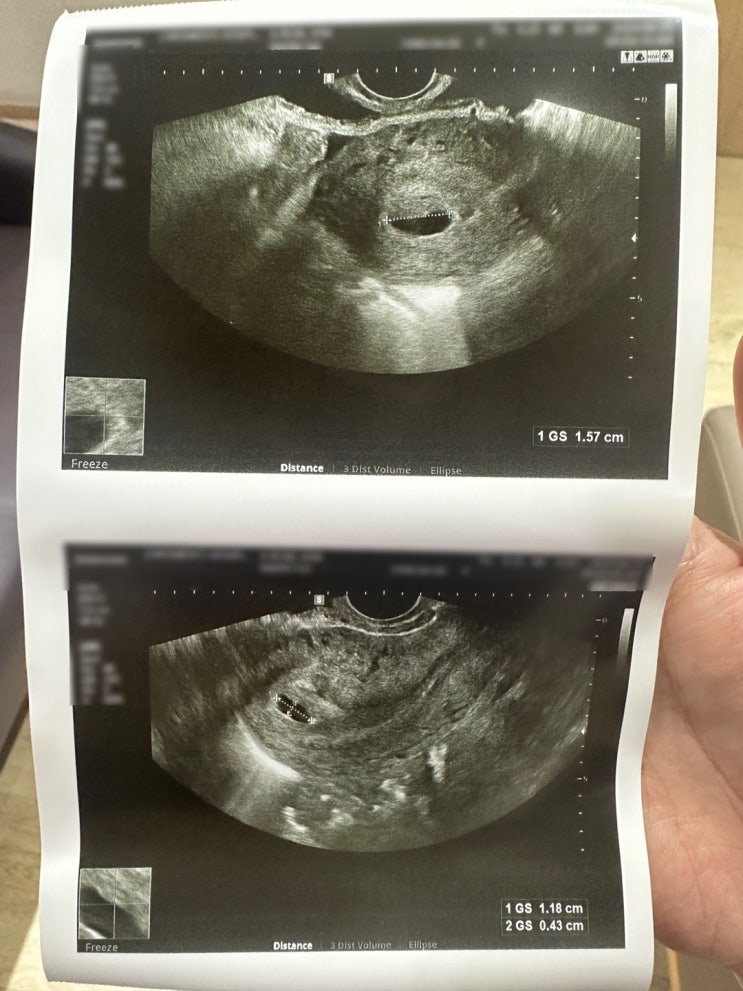

이른 아침, 더 이상 참지 못하고 남편과 전날 밤 올리브영에서 사온 원포 테스트기를 사용해 보았어요. 결...